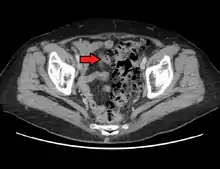

- على النقيض؛ الأشعة المقطعية هي الاختبار الأمثل في حالات النوبات الحادة لالتهاب الرتج وعند وجود مضاعفات.[39]